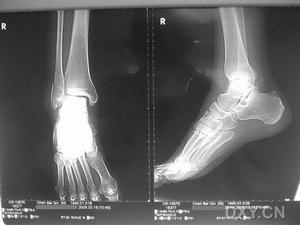

距骨骨折--Ⅱ型距骨頸骨折約占距骨骨折的30%。自高處墜落時,足與踝同時背屈,距骨頸撞在脛骨遠端的前緣,發生垂直方向的骨折。可分為三型:

Ⅰ型:距骨頸垂直骨折,很少或無移位。

Ⅱ型:距骨頸骨折合併距下關節脫位。距骨頸發生骨折後足繼續背屈,距骨體被固定在踝穴內,足的其餘部份過度背屈導致距下關節脫位。

Ⅲ型:距骨頸骨折合併距骨體脫位。距骨頸骨折後,背屈外力繼續作用,距骨體向內後方鏇轉而脫位,並交鎖於載距突的後方,常同時合併內踝骨折。常為開放性損傷。

(一)骨折類型:Ⅰ型骨折可用不負重的石膏固定踝關節於功能位6-8周。能獲得滿意的結果。Ⅱ型骨折需先作閉合復位,只有在足完全跖屈位時,才能得到整復。復位後先用石膏固定於跖屈位,6周后再更換功能位石膏,繼續固定6周。如閉合復位失敗,則行切開復位內固定。骨折癒合後才可負重。Ⅲ型骨折由於脫位的距骨體位於跟骨結節的內側,其上的皮膚被牽伸壓迫有發生壞死的危險,脛後神經血管神經末也有被壓迫造成前足壞疽及足底內側神經麻痹的威脅,因此整復是緊急的,距骨應立即進行整復。閉合復位時,可先將踝關節跖屈、跟骨外翻位牽引,將脫位之距骨體推向外側,使距骨體與載距突解鎖,再自踝後側將距骨體推向前方。亦可先在跟骨上貫穿一鋼釘牽引,使脛骨與跟骨之間的空隙增寬,再插入另一枝鋼針至距骨體內,鏇轉距骨,將其復位。然後,將足跖屈,整復距骨下脫位,復位後處理同Ⅱ型骨折。如閉合復位失敗,應立即行切開復位內固位。為了增加距骨的血液供應,預防距骨缺血性壞死,可同時作距下關節融合術。